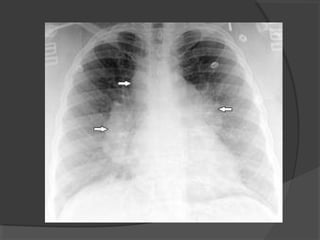

 Una nueva Rx reveló:

 El estudio del líquido mostró un pH

 El pacienteevolucionó con síntomas de sepsis asociados a una mayor dificultad respiratoria.  Una nueva Rx reveló:

 El estudiodel líquido mostró un pH de 6,4